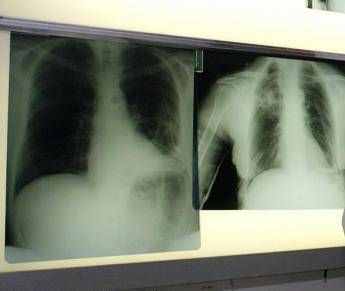

Bpco, ok dell’Ema alla prima terapia con propellente green